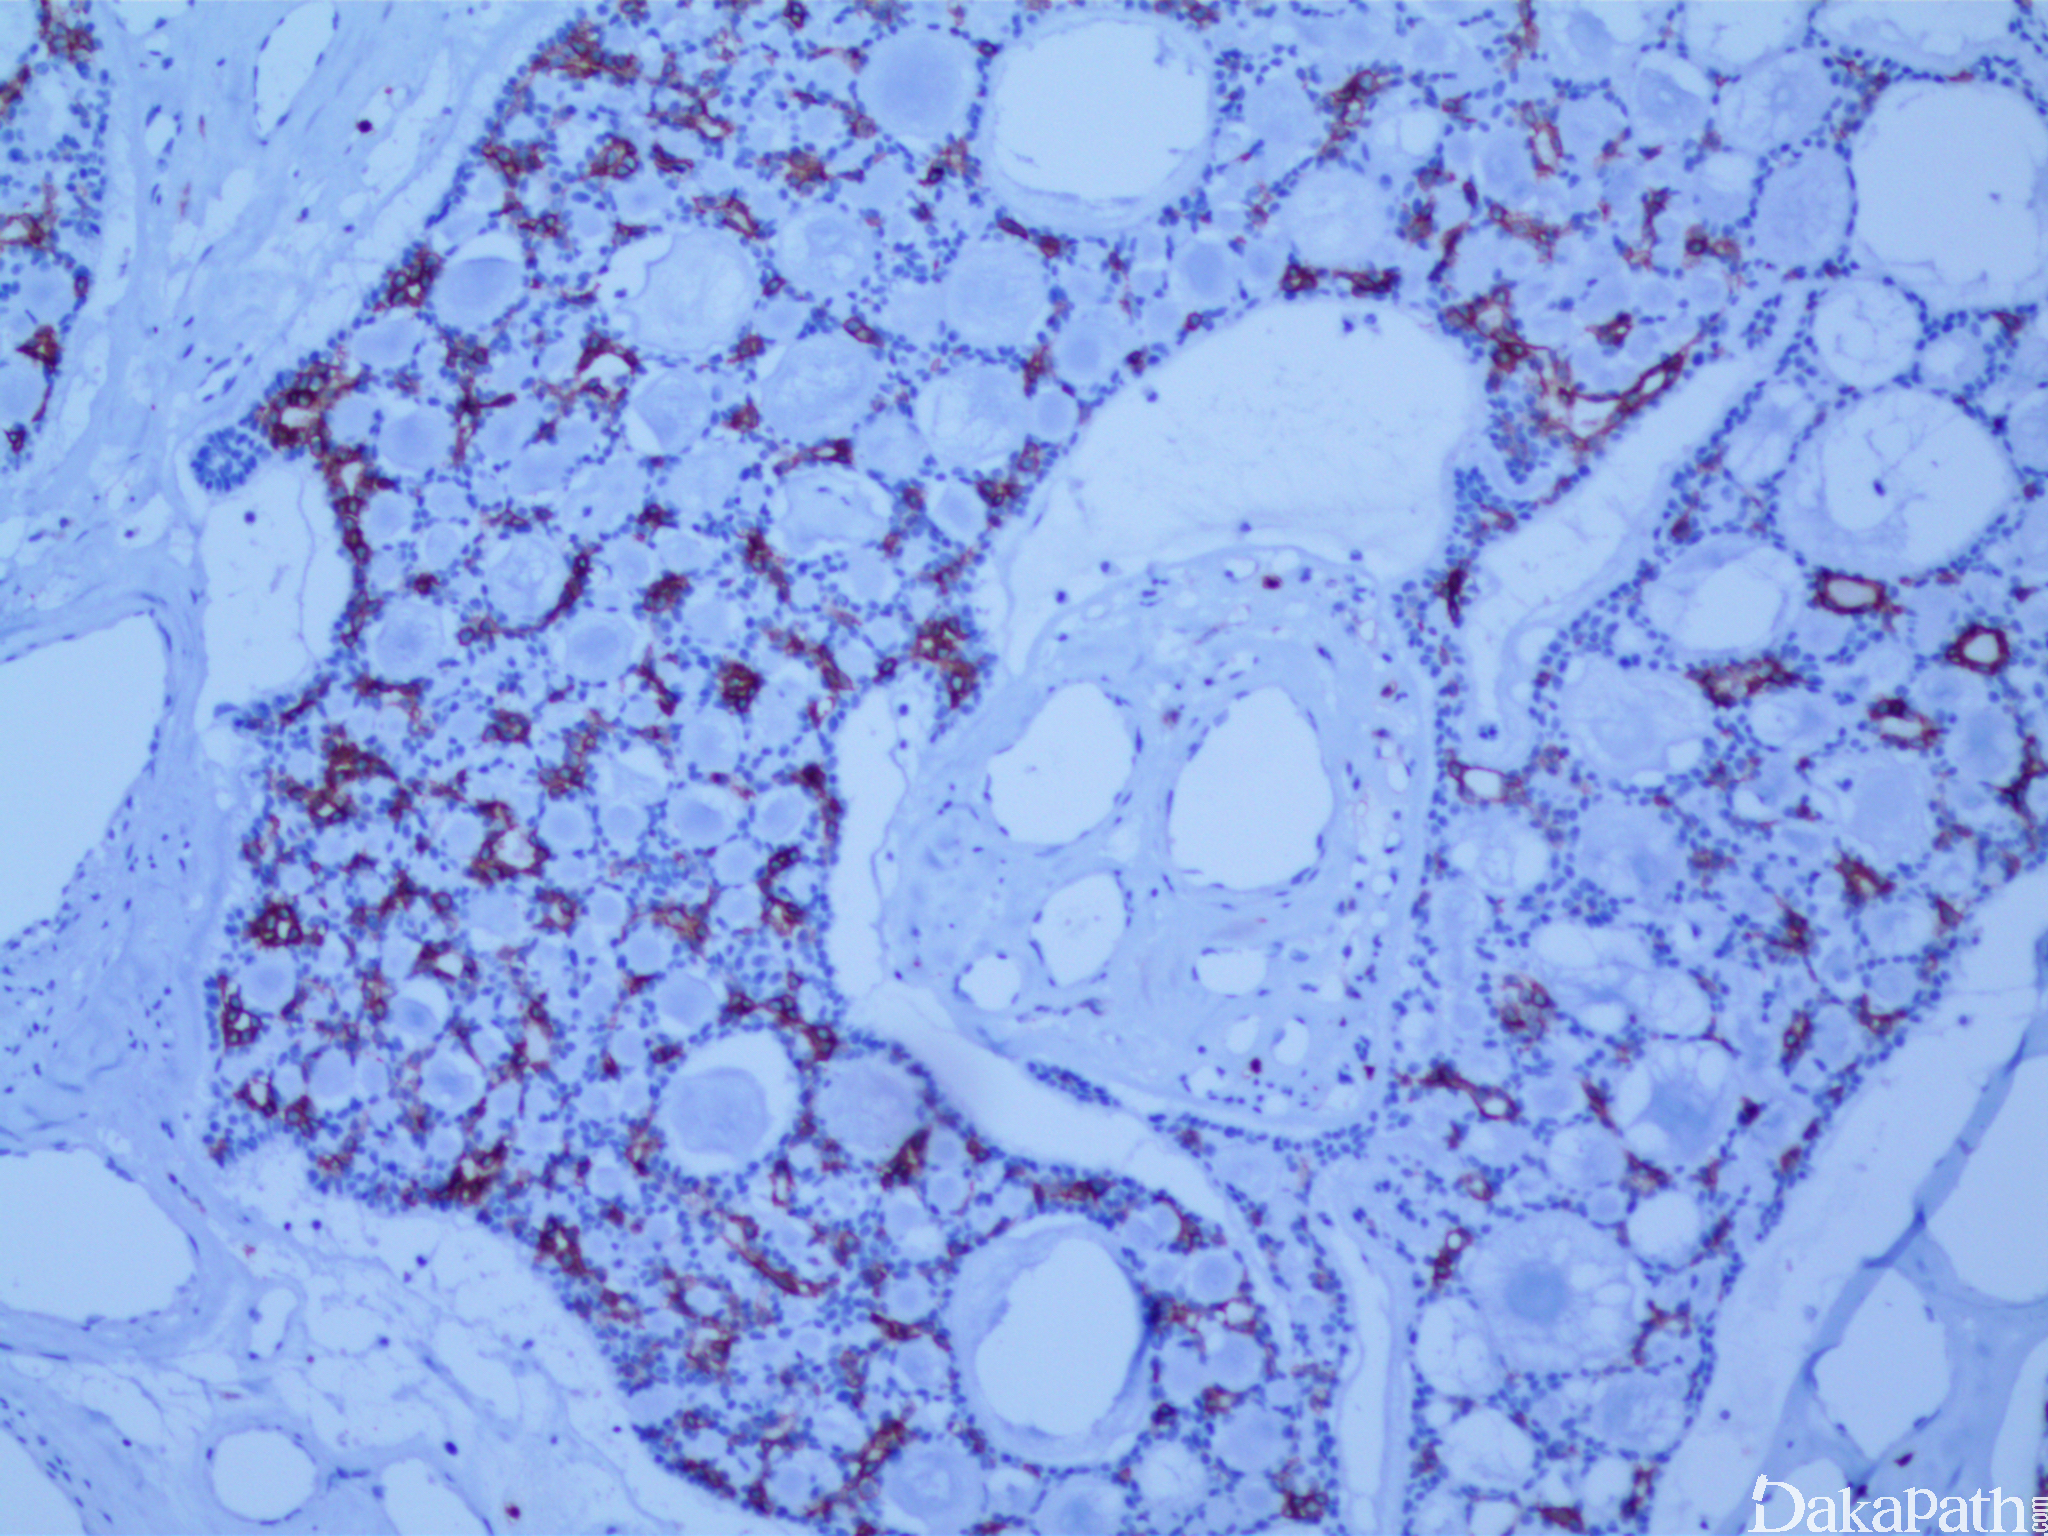

筛状型最常见,有两种类型筛孔,一种为假性腺腔,腺腔大小不一,多数为圆形、椭圆形或长圆形,内含均一的 AB 染色阳性物质或玻璃样变的胶原样物,可形成胶原小球样物质,假性腺腔周围有一层厚的基底膜。另一种是真性腺腔,数量较少,腔较小,内含嗜伊红分泌物,通常为 PAS 阳性的中性黏液,这些黏液经淀粉酶消化后依旧存在。

上皮细胞常表达 CD117. CK5/6. CK14. CK8/18. EMA、S-100 和 HE-cadherin 等;肌上皮细胞显示 Vim、CKl4. CK34βEl2. SMA、S-100. p63 阳性;基底膜物质 Ⅳ 型胶原和 laminin 阳性;大部分病例不表达 ER、PR 和 Her2。